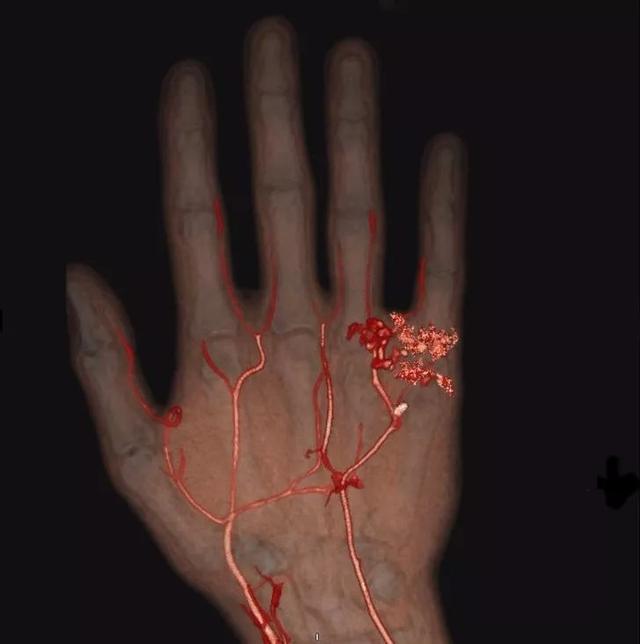

手部血管变性的CT图